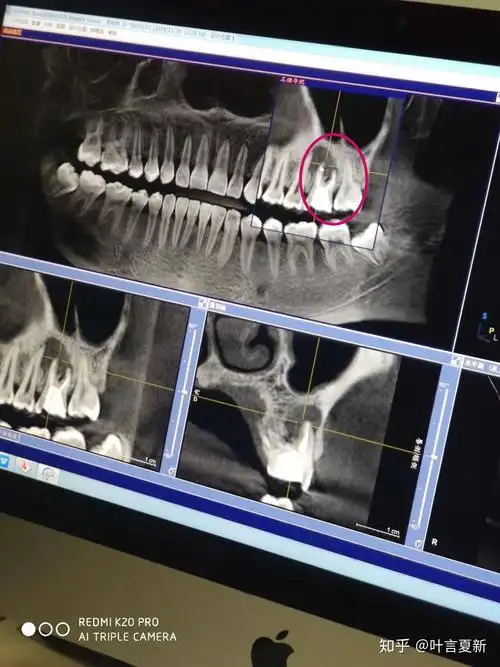

我的牙齿片子已经拍了,医生说有一个大的囊肿,请教,怎么办? - 知乎

阻生牙引起囊肿.朋友来种牙,拍完片子发现上颌大囊肿,内含一多 - 抖音